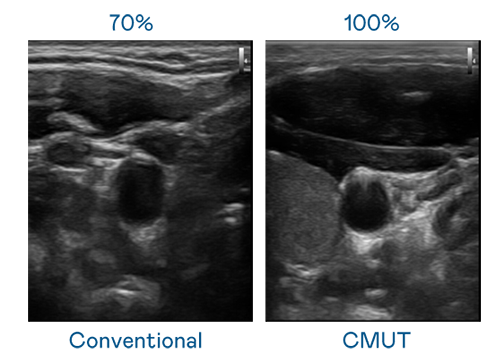

CMUT 技术是一种用电容式微机电元件来产生超音波讯号的技术。与传统 PZT 压电式技术相比,CMUT 频宽增加 30%,更宽频的超音波讯号让影像解析度大幅提升,是实现高影像品质医疗超音波扫描、促进精准医疗发展的关键技术。

大频宽带来超清晰影像

超音波影像的解析度高低,首先取决于探头能发出的讯号频宽。梦之城CITY OF DREAMS CMUT 可提供高清晰的超音波讯号,提供高频宽、高灵敏度、影像纹理细节更高的超音波影像,协助医护人员缩短影像判读时间及利用精准的医疗影像进行诊断。